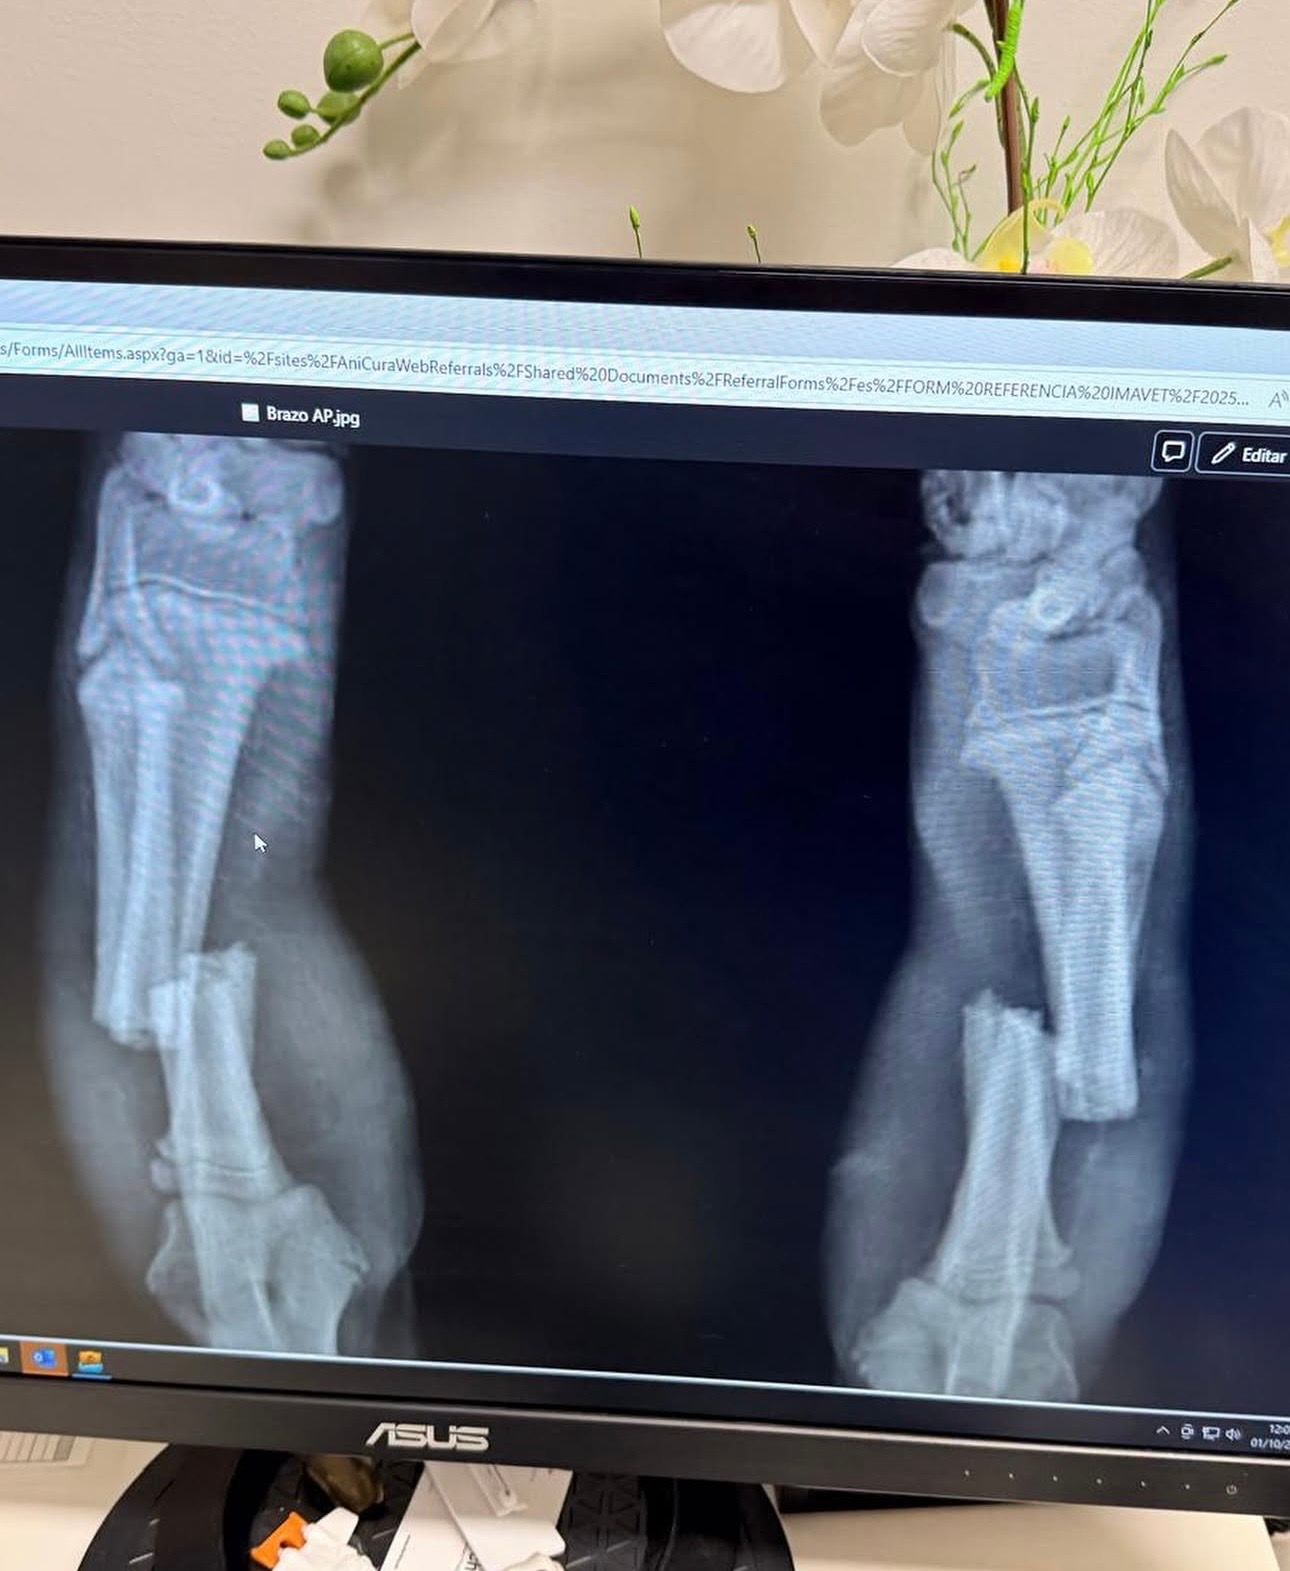

Pensaban que sólo tenía una pata rota, pero eran dos

Nada más rescatarla nos explica que la llevaron a un hospital veterinario en Santiago de Compostela dónde le hicieron una radiografía y descubrieron que tenía una fractura bilateral del radio en sus dos patas delanteras. No se sabe si esta lesión fue a causa de que alguien intentase atraparla y la agarrase por las patas, si pudo quedarse enganchada en algún lugar o si fue al realizar algún salto o mal movimiento. Pero lo que sí que saben es que la operación tiene un costo de 1.000 euros y es la que le va a devolver la vida y gracias a la que podrá llevar una vida como la de cualquier otro perro.